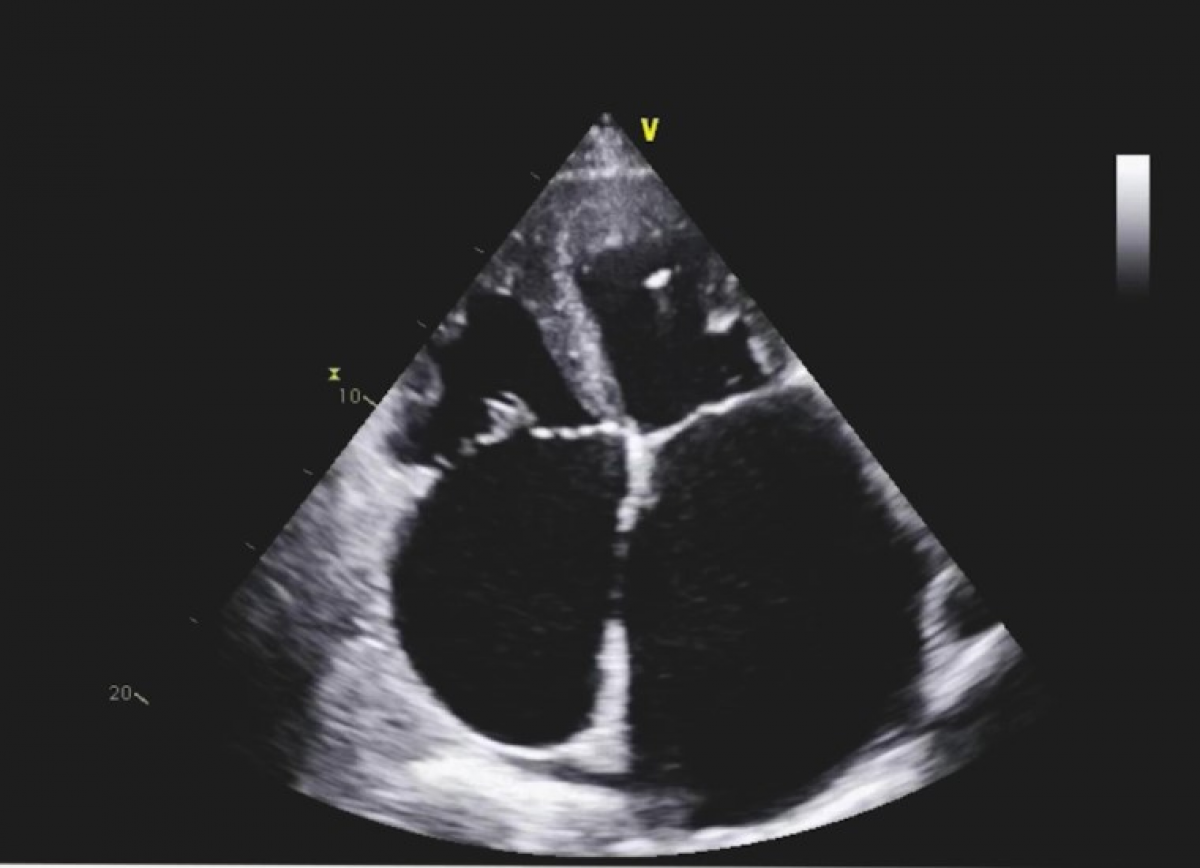

Pacjent z niewydolnością serca NYHA III i utrwalonym migotaniem przedsionków

Czynnościowa przedsionkowa niedomykalność mitralna.

Echokardiografia przezklatkowa

Ocena niedomykalności mitralnej.

Kwalifikacja do przezcewnikowego leczenia niedomykalności mitralnej.